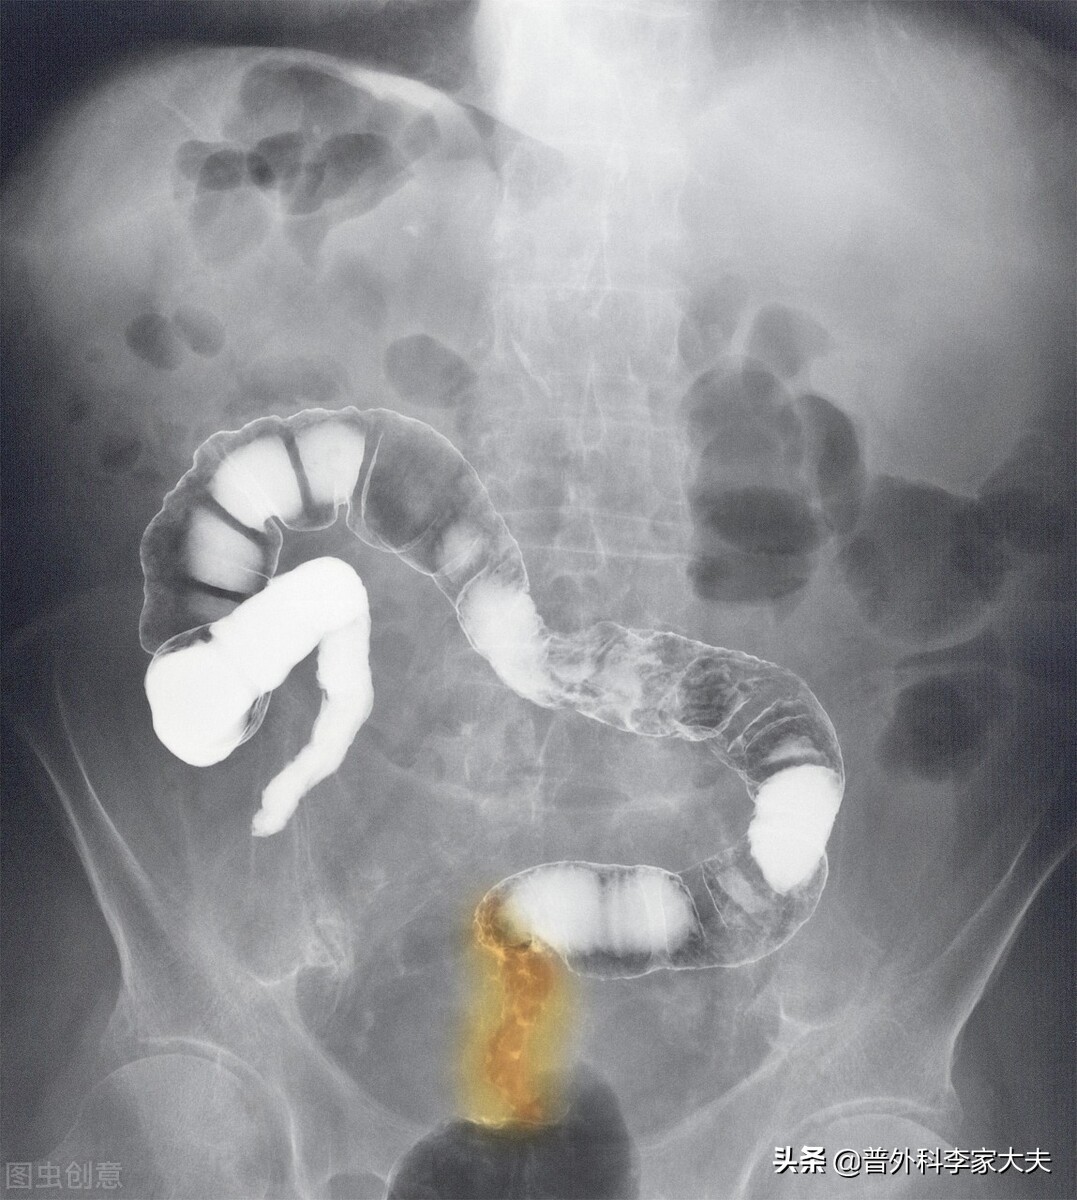

今天一位网友向我提问:“主任,我是中低位直肠癌Ⅱ期,新辅助治疗与肠癌根治手术都做了,术后病理检查也说我的肠癌根治到位,不是高危型肠癌病理组织类型,可以不用化疗。可为何我直肠癌术后三年半,又复发了?”

临床病理分期为直肠癌Ⅱ期的患者,是通过影像检查确定的,而众所周知,影像检查仍然有很大的局限性,通常影像检查是难以发现小于3mm以下肠癌微小转移病灶,当然更小的转移的癌细胞更是发现不了。而术后源自病理检查的肠癌病理分期,由于是受限于病理标本的局限性。因此,肠癌的病理分期,不管源自影像,还是来源于病理检查的病理分期,仍然会因设备与人为因素等,导致目前难于避免的错误发生。

比如,本文这位术后出现肠癌复发的直肠癌Ⅱ期的患者,它的病理分期可能就是错误的。从他术后直肠癌复发的事实告诉我们,患者体内早已存在发生转移的肠癌细胞或微转移病灶了,他事实上已经是发生了淋巴转移或血行转移的Ⅲ、Ⅳ型肠癌患者了,只是手术前后均未及时发现而已,直到肠癌复发,才让事情得己真相大白了。